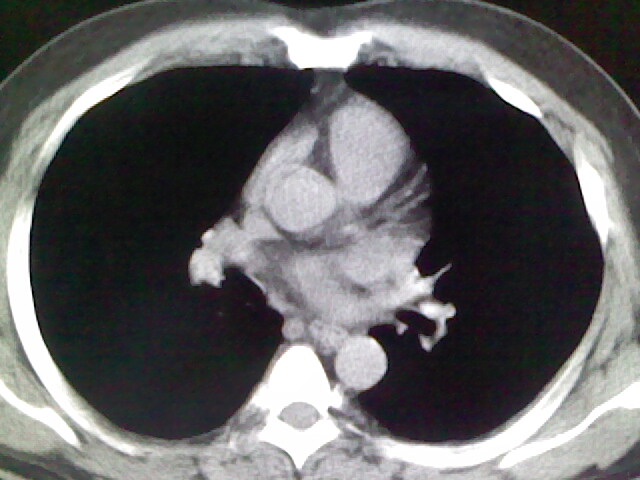

标题: CT17932:临床怀疑肺栓塞

男,34岁,自觉右侧胸痹,胸闷3天余

左上肺局限片状透光度增强区,肺纹理稀少,可考虑局限性肺气肿。

左上肺局限性肺透光度减低,肺纹理稀少;这虽然符合早期肺栓塞的改变,但与局限性肺气肿难以鉴别。

书上讲早期肺栓塞就是表现肺透光度减低,肺纹稀少。